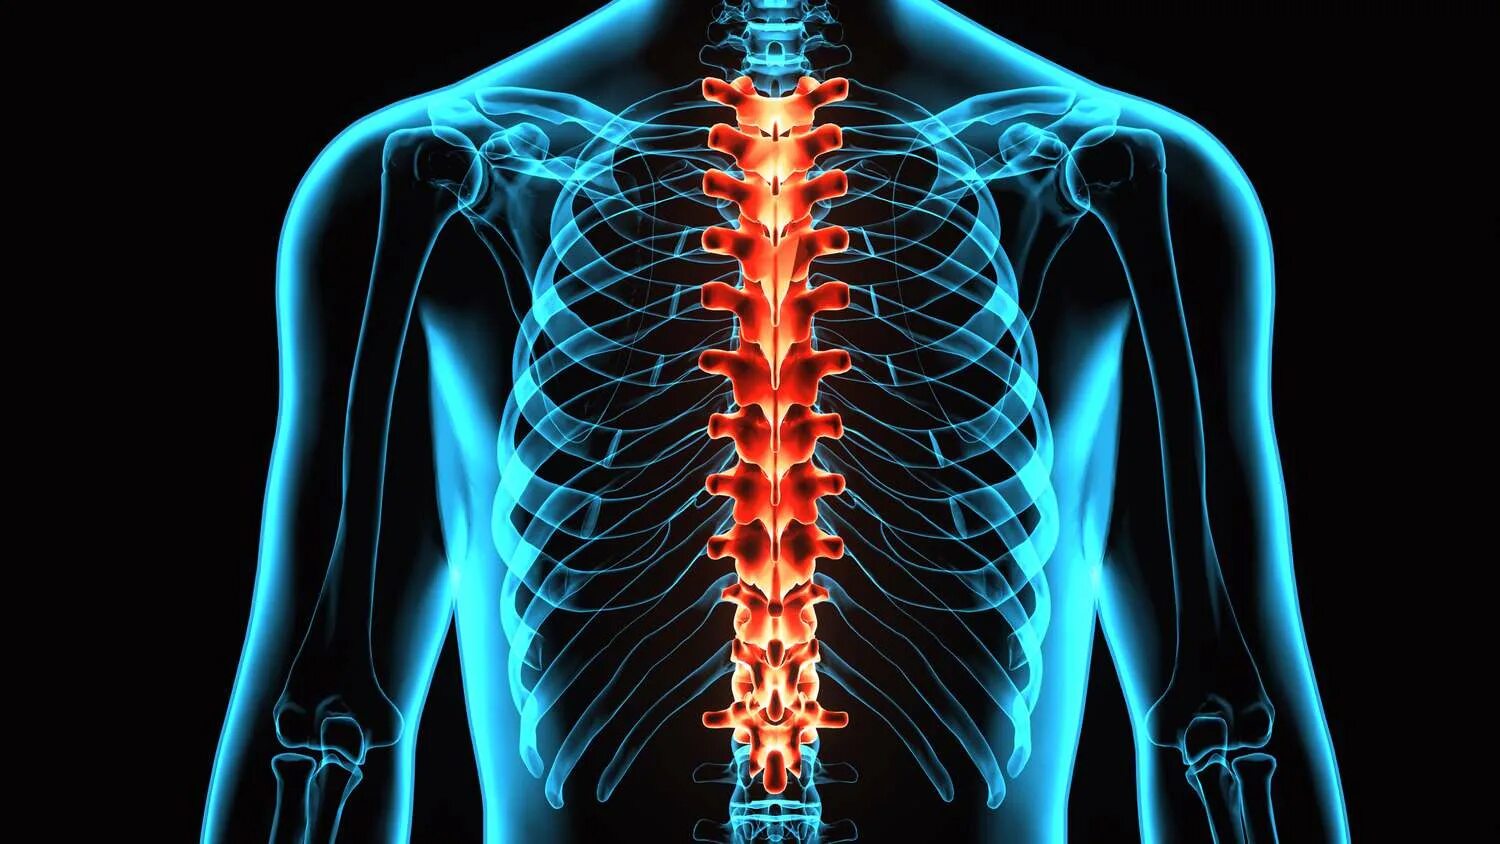

Backbone s